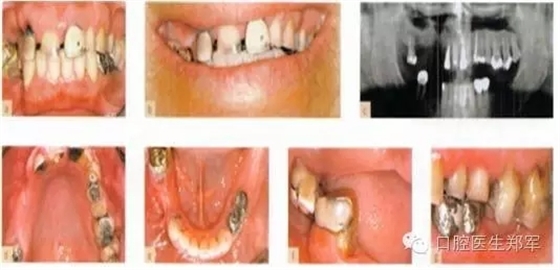

圖片5到12案例介紹了部分牙列缺損導(dǎo)致的功能缺失和美學(xué)受損。

形態(tài)缺陷的診斷包括:牙列缺損、后牙支撐減少、輕度到中度的垂直距離喪失,美學(xué)和功能障礙,以及不良修復(fù)體。

口腔疾病和功能障礙包括:繼發(fā)齲、可復(fù)性關(guān)節(jié)盤移位、繼發(fā)創(chuàng)傷、臨床附著喪失≥5mm超過30%的位點(diǎn)的嚴(yán)重慢性牙周炎。

圖5 a-g 局部缺牙、美學(xué)缺陷、牙列缺損、后牙牙合支撐喪失、部分牙段過度萌出、咬合垂直距離中度喪失(圖片由Dr. 0 Ghelfan提供) |